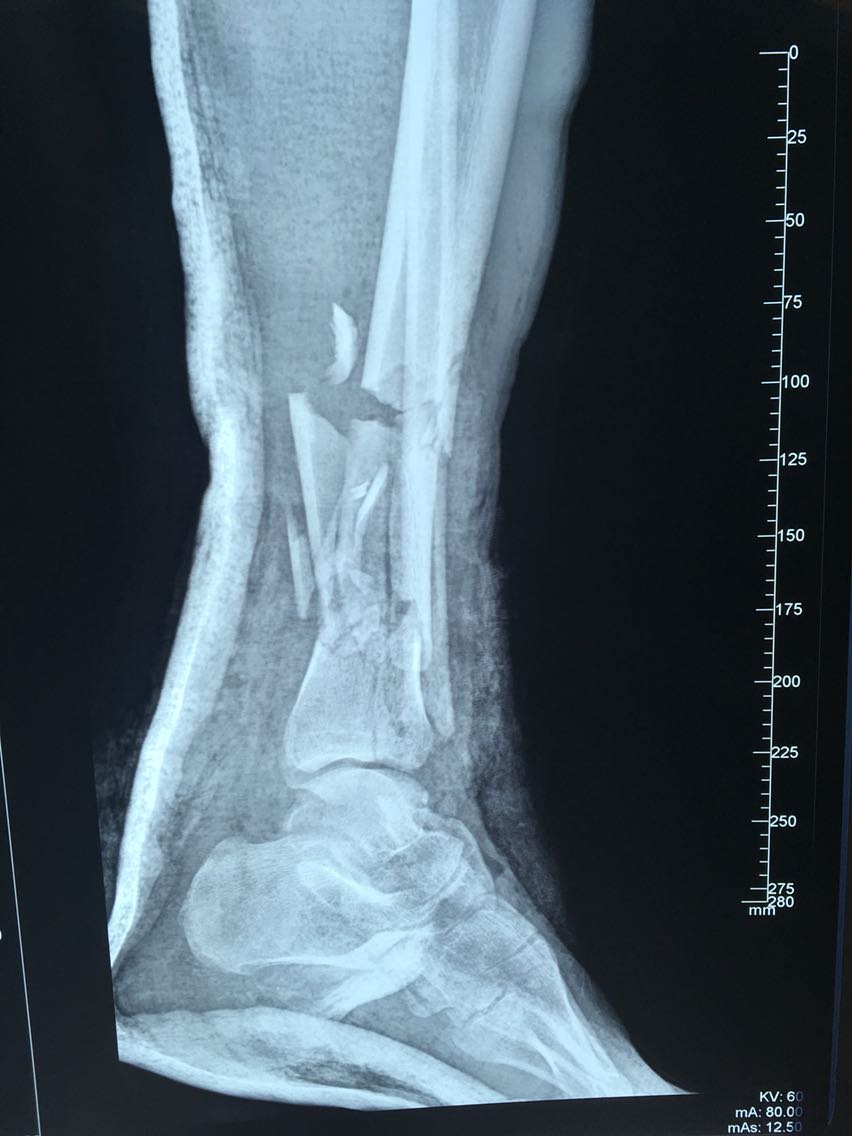

查体:左下肢肿胀,腓骨下段外侧皮肤、足背外侧皮肤碾挫严重,外踝部骨质外露,左小腿下段可触及骨擦感,出现反常活动,足背动脉可触及,左下肢皮肤感觉过敏,皮温略低,末梢毛细血管充盈未见明显异常。 辅查:左胫腓骨远端骨质碎裂,骨折端移位,骨折线波及胫距关节面,下胫腓关节间隙消失;左跟骨、骰骨骨质碎裂,骨折块移位,跟骰关节受累。

诊断:车祸伤:1.左胫腓骨远端开放性粉碎性骨折2.左跟骨开放性粉碎性骨折3.左骰骨粉碎性骨折 治疗:急行清创探查骨折复位外固定架固定治疗。